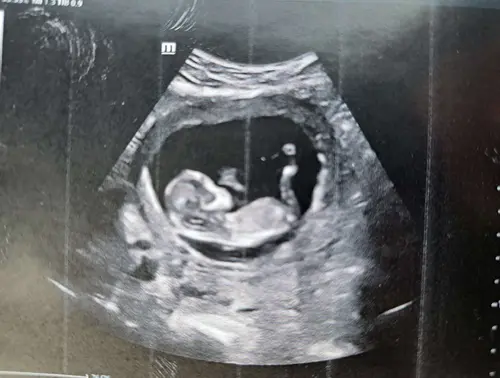

Hallo, Kent iemand de skull theorie? Wat denken jullie? 馃┓馃┑